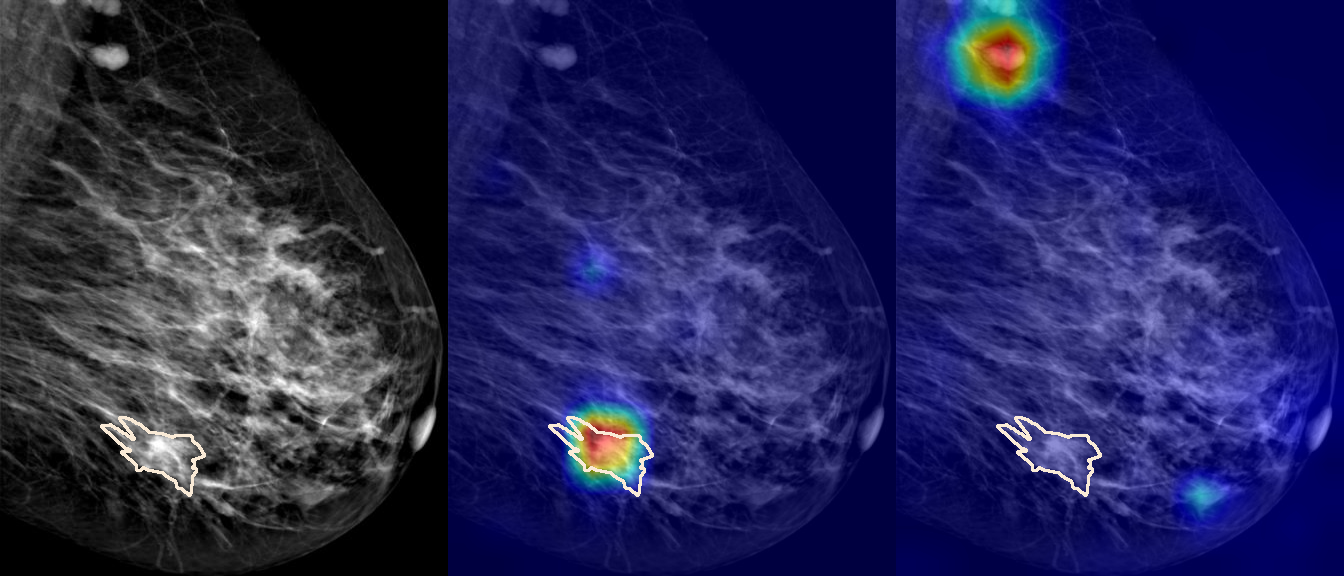

To interpret the decision-making process behind the quantitative results, we visualized Class Activation Maps (CAM) for the top-performing methods, ERM and VREx. Figures 1 through 2 illustrate discriminative regions identified by the models within the full mammograms.

Localization of Clinical Features: A key concern in medical AI is whether high performance stems from genuine pathology detection or spurious background correlations. Our visualizations suggest that Standard ERM achieves its superior quantitative performance by predominantly prioritizing clinical cues. As shown in the top rows of the Figure 1 and Figure 2, the ERM-trained models consistently focus attention on the specific lesion regions within the breast tissue. This demonstrates that despite lacking explicit invariance constraints, ERM is capable of learning robust, medically relevant features when trained on diverse multi-source data.

Attention Drift in Both Methods: While both ERM and VREx generally identify the correct region of interest in successful cases, neither method is immune to attention drift. We observe instances in both training paradigms where the model focuses on irrelevant areas, such as healthy fibroglandular tissue or background artifacts (e.g., rows 5 and 6 in Figure 1). This indicates that while VREx is designed to penalize instability, it does not guarantee perfect anatomical focus compared to the unconstrained ERM baseline.